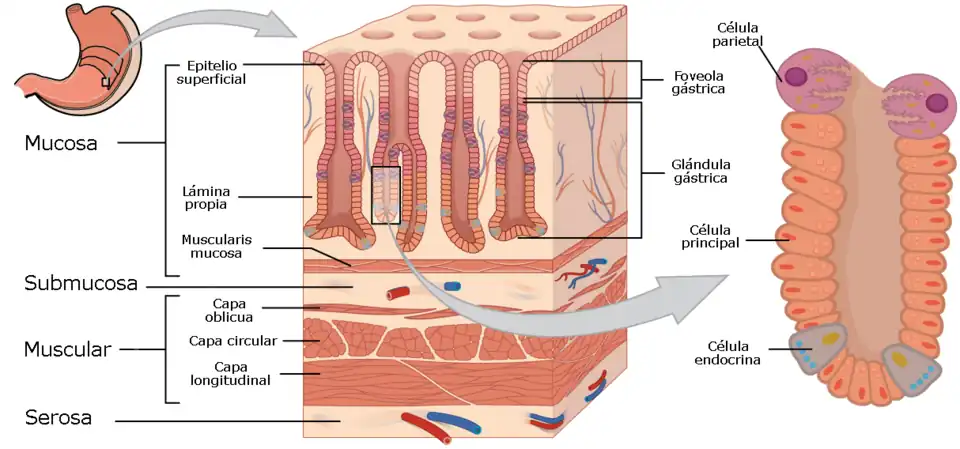

La gastritis es una enfermedad del estómago que se define como la inflamación de la mucosa gástrica.[1] El diagnóstico preciso se obtiene por exploración endoscópica. Dependiendo del aspecto de la mucosa se ha clasificado en gastritis erosivas y no erosivas. También se clasifican en agudas y crónicas, en esta última puede existir algún grado de atrofia (gastritis atrófica). Las causas son muy variadas, entre ellas, los malos hábitos alimentarios, el estrés, ingesta de alimentos a deshoras, el abuso en el consumo de antiinflamatorios no esteroideos (aspirina, piroxicam, indometacina, ketoprofeno, etc.), infección por Helicobacter pylori y trastornos autoinmunes como en la gastritis atrófica con presencia de autoanticuerpos y la enfermedad celíaca.[2][3][4]

El diagnóstico se realiza por medio de la endoscopia del aparato digestivo superior.[5] En el examen histopatológico de los tejidos se observa infiltración de leucocitos polimorfonucleares.

Principales tipos

- Gastritis crónica atrófica. Se caracteriza por inflamación del revestimiento del estómago que se presenta gradualmente y que persiste durante un tiempo prolongado. La gastritis crónica puede aumentar el riesgo de desarrollar cáncer de estómago cuando la inflamación crónica de la mucosa gástrica provoca la atrofia o la aparición de metaplasia intestinal, lo cual está directamente relacionado con la posible progresión hacia el cáncer gástrico. La evolución conduce a desaparición de los pliegues (se observan los vasos sanguíneos de la submucosa), disminución del número de glándulas y finalmente metaplasia intestinal. La gastritis crónica atrófica que ha evolucionado a metaplasia intestinal es un factor de riesgo para la aparición de cáncer de estómago. Pueden clasificarse en dos grupos:

- Gastritis erosiva. Se caracteriza por erosiones superficiales y múltiples en la mucosa del estómago, suele producirse por ingesta de antiinflamatorios no esteroideos y puede provocar la aparición de hemorragia digestiva. En algunos casos puede evolucionar a úlcera péptica.

- Gastritis eosinófílica. Se caracteriza por infiltración por eosinófilos de cualquier capa de la pared del estómago.